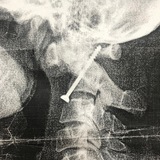

🔪 Анамнез: в результате бытового конфликта произошло ранение головы ножом. На момент ранения пострадавший был в сознании, далее в связи с нарастанием неврологической симптоматики произошло угнетение сознания, плюс седация, выполненная бригадой скорой помощи.

💀 Диагноз: Тяжелая открытая проникающая черепно-мозговая травма колюще-режащим предметом, ушиб головного мозга тяжелой степени, гемотампонада желудочковой системы головного мозга.

💉 Оперативное лечение: Выполнено экстренное дренирование желудочковой системы (убрана кровь из желудочков мозга). Для того, чтоб вынуть нож (вне операционной категорически нельзя было трогать): выполнена церебральная ангиография (исследование сосудов головного мозга с контрастом) для определения какие сосуды повреждены и могут вызвать фатальное кровотечение при изъятии ранящего предмета (нож).

🩻 По ее результатам: имеется повреждение внутренней сонной артерии, поэтому была выполнена одномоментная эмболизация (закупорка) поврежденого сосуда и изъятие ранящего снаряда.

📸 Представленные фотографии: внешний вид раненного, компьютерная томография головного мозга, 3D-реконструкция томографии.